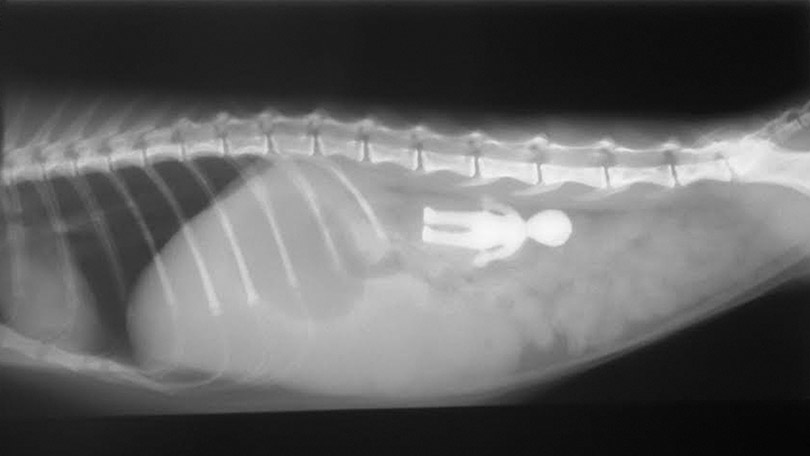

Veterinary Medical and Surgical Group San Juan. Young cats and young large-breed dogs are more likely to present with signs of foreign body obstruction than older animals. Often the foreign body cannot be seen on the x-ray but the consequences of the foreign body obstruction are visible. Clinical signs are variable depending on duration degree and location of the foreign body but often include vomiting and anorexia. Gastrointestinal foreign bodies are an important differential diagnosis for patients presented for vomiting and radiography remains the main initial imaging modality in these cases.

In most cases a veterinarian will assess the dogs condition with X-rays or other imaging scans to determine the safest and most effective approach. Gastric foreign body is a term that refers to any material other than food that is eaten and that results in a serious digestive problem in the stomach. If a foreign body becomes stuck at any point in the digestive tract from the mouth to the esophagus stomach or intestines so that it partially or completely blocks the flow of nutrients and impairs blood flow to the bowel then the foreign body becomes a life-threatening obstruction. The string may cut through the frenulum of the tongue and bury. Often the foreign body cannot be seen on the x-ray but the consequences of the foreign body obstruction are visible.

Young cats and young large-breed dogs are more likely to present with signs of foreign body obstruction than older animals. Several views or a series of specialized X-rays using contrast material barium or other radiographic dye will often be necessary. Black arrows define margins of suspected foreign material. They will pump air into his stomach or make use of Barium to locate any blockage. Often the foreign body cannot be seen on the x-ray but the consequences of the foreign body obstruction are visible.

Diarrhea weight loss lethargy and signs of septic. They will pump air into his stomach or make use of Barium to locate any blockage. In addition your veterinarian may recommend blood and urine tests to assess whether the patients health has been compromised by the obstruction or to rule-out other. Radiographs revealed a foreign body in a distended stomach. The procedure used for foreign body removal in dogs will depend on the nature and location of the obstruction.